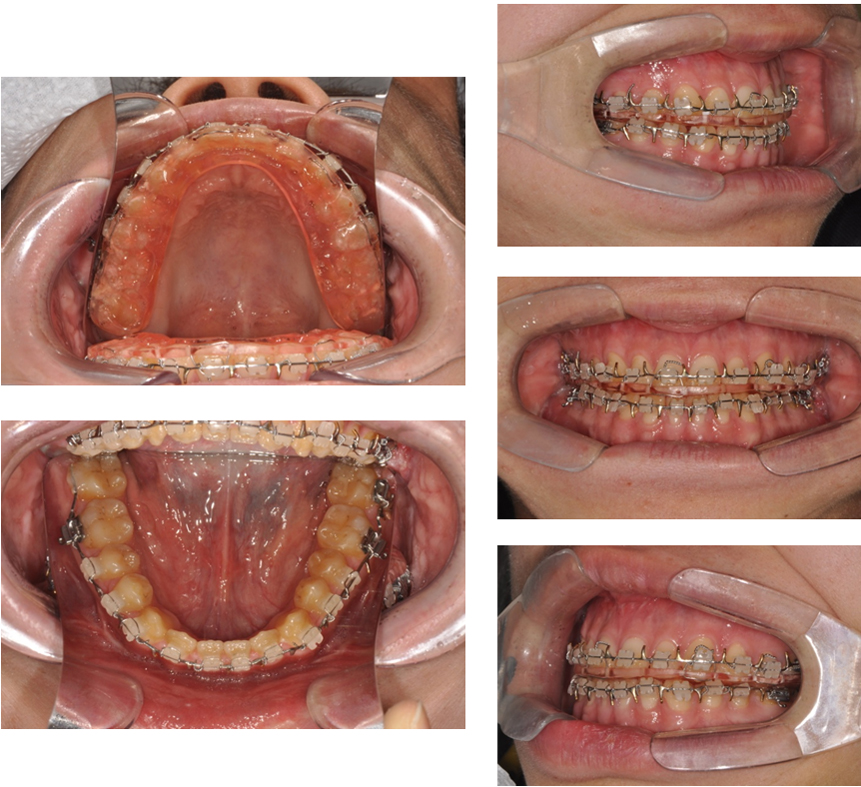

실제로 연세고운미소치과의

선수술케이스를 보겠습니다

아래턱이 나오고 비대칭있는 분이십니다.

본을 떠보니 선수술이 가능해서

선수술을 시행하였습니다.

브라켓 달아놓고

수술을 위한 준비가 완료됐습니다

외모가 나빠지지 않고

바로 수술을 할수 있으며

전체 치료기간도 줄어들수

있습니다.

장치제거후 모습입니다.

수술과 교정이 잘 마무리 된것을

볼수 있습니다.